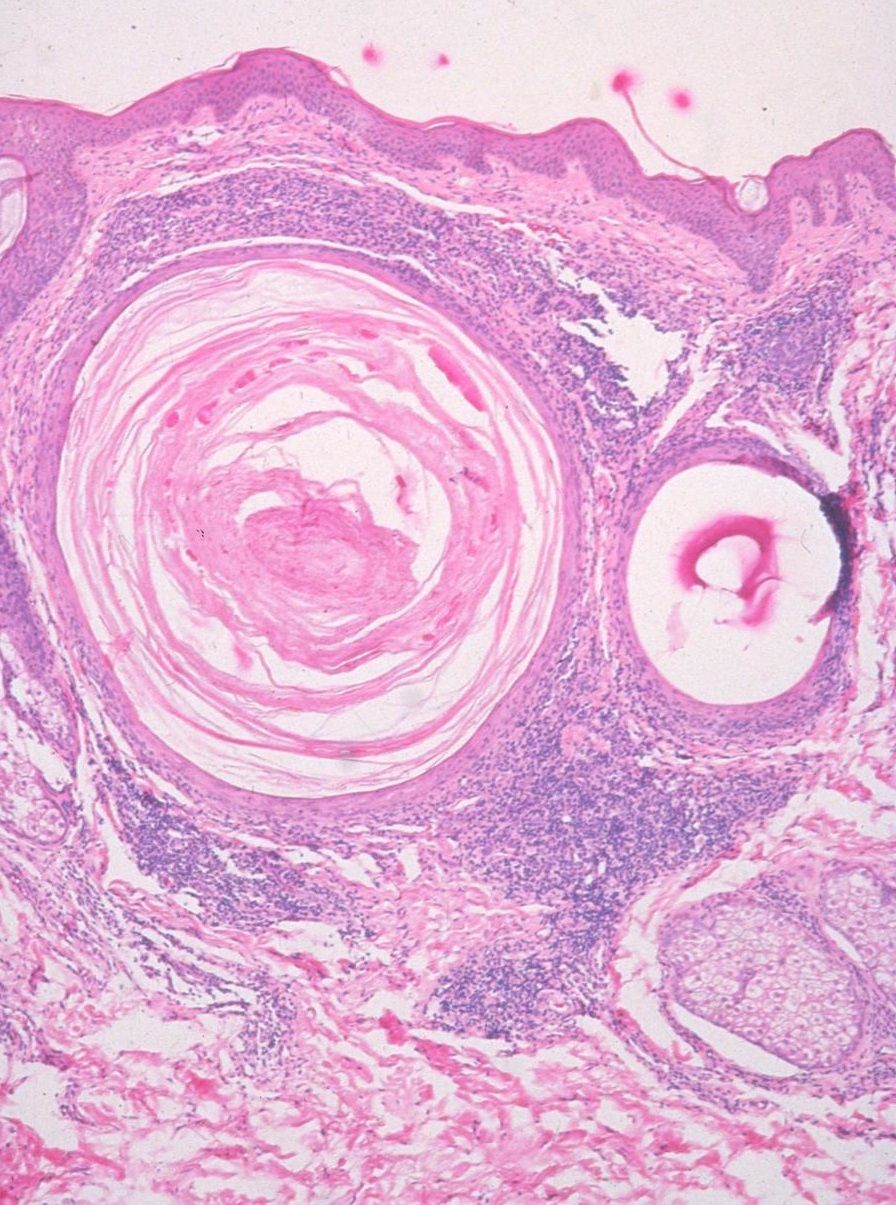

Se tratan de quistes de queratina. La queratina es una proteína que se halla en la capa más superficial de la piel, en el estrato córneo.

Los milium aparecen cuando crece en exceso sobre un poro y los restos de la piel o grasa quedan atrapados debajo de la superficie. Por eso aparece un punto blanco que se asemeja a un grano.

De igual manera, otro indicador es que, al tratar de eliminarlo mediante la presión de nuestros dedos, no sale nada. Esto se produce porque la bola blanca queda aprisionada por un cúmulo de piel queratinizada que no tiene un punto de salida. Al contrario que un punto negro o una espinilla, que si debería salir.